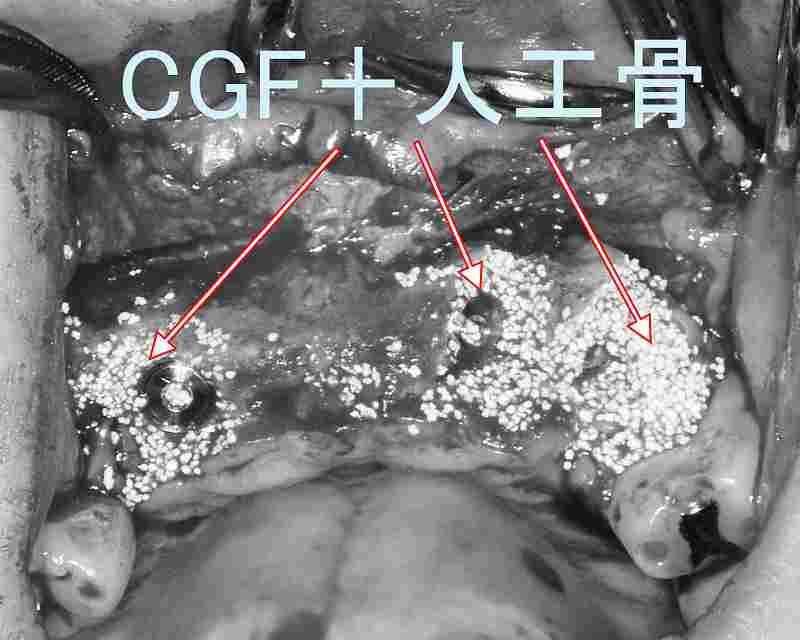

その際に用いるのが**GBR(骨再生誘導法)やサイナスリフト(上顎洞挙上術)**です。人工骨やCGFと呼ばれる自己血液由来の成長因子を併用し、メンブレンで覆って骨の再生を促すことで、インプラントに必要な骨量を確保します。上顎奥歯部では、上顎洞底を押し上げて骨を増やすサイナスリフトを行うこともあります。これらは高度な技術を要するため、経験豊富な歯科医による精密な診断が不可欠です。